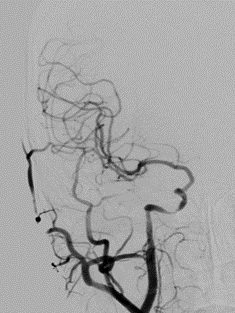

2021-12-3 DSA

重要影像结论:2021-6-25右侧基底节区新发脑梗死,2021-12-3提示右侧颈内动脉海绵窦段重度狭窄。

DSA

重要影像结论:左侧颈内动脉C4段重度狭窄。